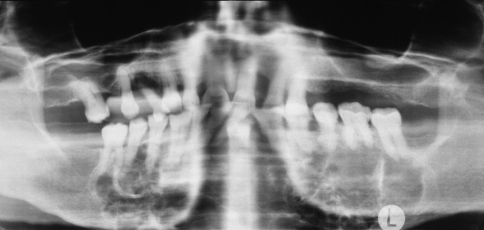

The glandular odontogenic cyst most frequently occurs in middle-aged adults and has a predilection for the anterior mandible, with many cases crossing the midline. Many examples of so-called “median mandibular cyst” probably represent glandular odontogenic cysts. Maxillary examples also are seen most often in the anterior region. The clinical presentation is highly variable, ranging from small, asymptomatic unilocular cysts less than 1 cm in diameter to large, expansile, multilocular lesions that destroy much of the jaw (Fig. 5).

Fig. 5.

Glandular odontogenic cyst. A large, expansile, multilocular radiolucency involves the entire body of the mandible from molar to molar